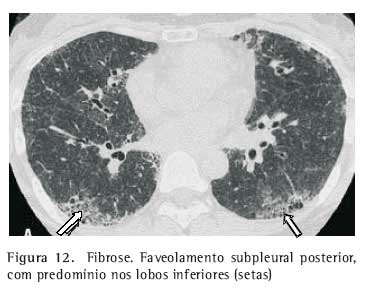

Fibrose. As anormalidades parenquimatosas podem evoluir para fibrose, que está associada a distorção arquitetural, perda volumétrica, opacidades lineares, faveolamento, massas fibróticas, bronquiectasias e bronquiolectasias de tração, usualmente nos campos pulmonares médios e superiores (Figuras 11 e 12)(7).